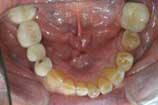

Let me cite a real-life case as an example. (The full-face photo in this case is eliminated for the sake of the patient's privacy.) As we — the patient, my assistant, and I — reviewed the pictures, the patient first noted the brightness of the old porcelain fused to metal crown on his lateral incisor. Then, in the close-up smile photo, he noted the contrast between that tooth and the cuspid behind it. (Figure 1). When he saw the retracted view, it was obvious even to this nondentist that there was something very wrong with his lower plane of occlusion. (Figure 2). He also noticed the exposed PFM margins. This allowed us to explain how the supra gingival margins of Empress restorations would not develop this problem down the road. In the upper occlusal photo, the hole in the crown and the fractured crowns were very apparent, as was the wear and old fillings on his front teeth. (Figure 3.) The wear and irregularities of the lower teeth were also obvious to him. (Figure 4.)